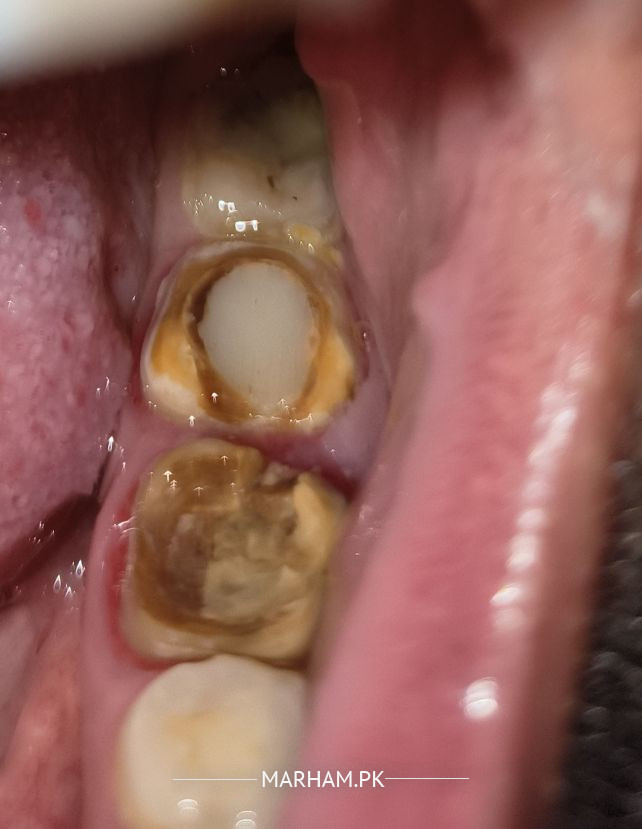

Assalam alaikum doctors mei ney apney 2 dant ki root canal karwahi thi phir Kuch din Baad crown lagwa Liya but yeh crown zaida properly fix nai Howa mei pochna cha Raha tha k yeh merey dant mei hole hai is ko clean kar k laser filling Karwana safe hai or teeth ki blackness b saaf ho jahey in future Khana khaney mei masla na ahey abhe donuo dant death hai , please suggest me best solution for it .

This crown looks very old and worn down..

It is advisable k aap check karwaye and get new crowns fixed.. Without crown apkay daant tootny k khatara hai aur root canal fail hoskti hai.

The teeth in a very bad condition so it’s best to remove them both and get dental implants

these teeth can be saved although they are in poor condition but needs proper evaluation and an experienced dentist

ap dobara sa crown kra lein achy clinic sy dentist properly evaluate kery ga or apko further guide kry ga...huygiene achi rkhy mouth ki bki teeth bi affect ho skty hein.

Yes you should get filling done for one tooth and my advice is to go for a new bridge with proper crown preparation for better results.

first of all do properly fill the tooth then clean the surrounding areas and then make new bridge .